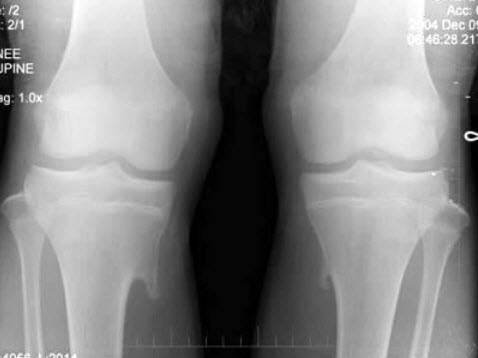

83、单项选择题

男,14岁,偶然发现双膝部肿块1天,双膝关节摄片如图,最可能的诊断是()

A.骨瘤

B.骨软骨瘤

C.局限性骨皮质增厚

D.软骨肉瘤

E.以上均不正确